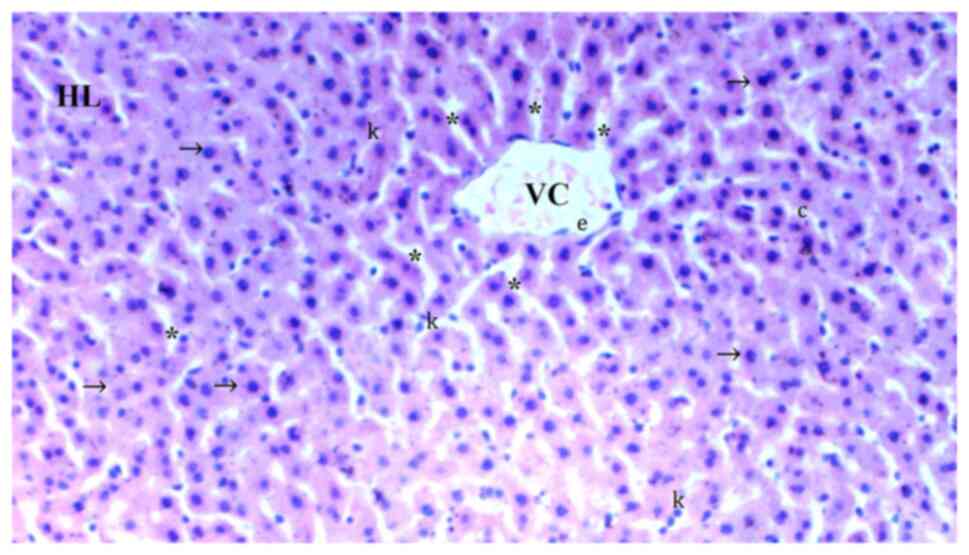

In comparison with the control group (Fig. 1), hydropic degeneration was more common in IR (P<0.0001; Fig. 2). Hydropic degeneration was found to be significantly lower in Co (Fig. 3), IRS (Fig. 4), Co + IR (Fig. 5) and Co + IRS (Fig. 6) groups compared with those in the IR group (P=0.001, P=0.026, P=0.003 and P=0.003, respectively; Table I).

Representative light microscopy of hepatic tissue from the control group. Normal liver tissue. Magnification, x100. HL, hepatic lobule; VC, vena centralis; k, Kupffer cell hyperplasia; *, sinusoid dilatation; ↓↓, infiltration; →, hepatocyte; c, dikaryotic hepatocyte; con, congestion.